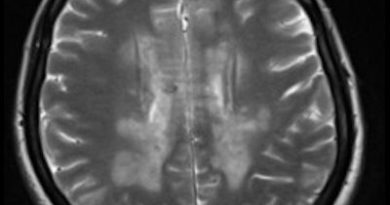

- A) Aksiyel T1A, T2A, T1A C+ ve sagittal T2A sekanslarda, sol seviye 3’te, karotid arterleri anteriora iten (ok), düzgün sınırlı, T1A hafif kasa göre hiperintens, heterojen iç yapıda, T2A hiperintens, içerisinde tübüler hipointens alanlar (flow-voids) içeren (ok), belirgin kontrastlanan (ok) kitlesel lezyon izleniyor. Kontrast sonrası T1 görüntülerde belirgin ve homojen kontrast tutulumu izleniyor (ok).

- B) BT anjiografi incelemesinde, aksiyel ve sagittal kesitlerde, solda tariflenen lezyon belirgin hipervasküler olup internal ve eksternal karotid arteri arteriora itmiştir (ok). Bulgular vagal paragangliom ile uyumludur. Ayrıca sağ karotis arter bifurkasyonda (ok), boyun MR’da net seçilemeyen, benzer özelliklerde, milimetrik, karotid cisim paragangliomu ile uyumlu ayrı bir hipervaskuler lezyon (ok) daha izleniyor.

- Vagal paragangliomalar, karotid arterin arkasında yerleşme eğiliminde olup internal ve eksternal karotid arteri anteriora, internal jugular veni posteriora iterler. Karotid bifurkasyonu genişletmezler.

- MR’da T2 ağırlıklı görüntülerde flow-voidlar, belirgin kontrastlanma; BT anjiografide arteriyel fazda belirgin kontrastlanma (lightbulb sign) paragangliomaların ayırt edici özellikleridir.